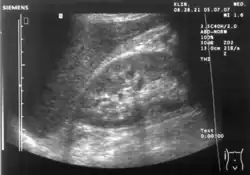

Ultrasound of liver (left side of the image) and right kidney (right side of the image) and Morison's pouch, not containing fluid -

Ultrasonographic view of the abdomen demonstrating fluid within Morison's pouch -